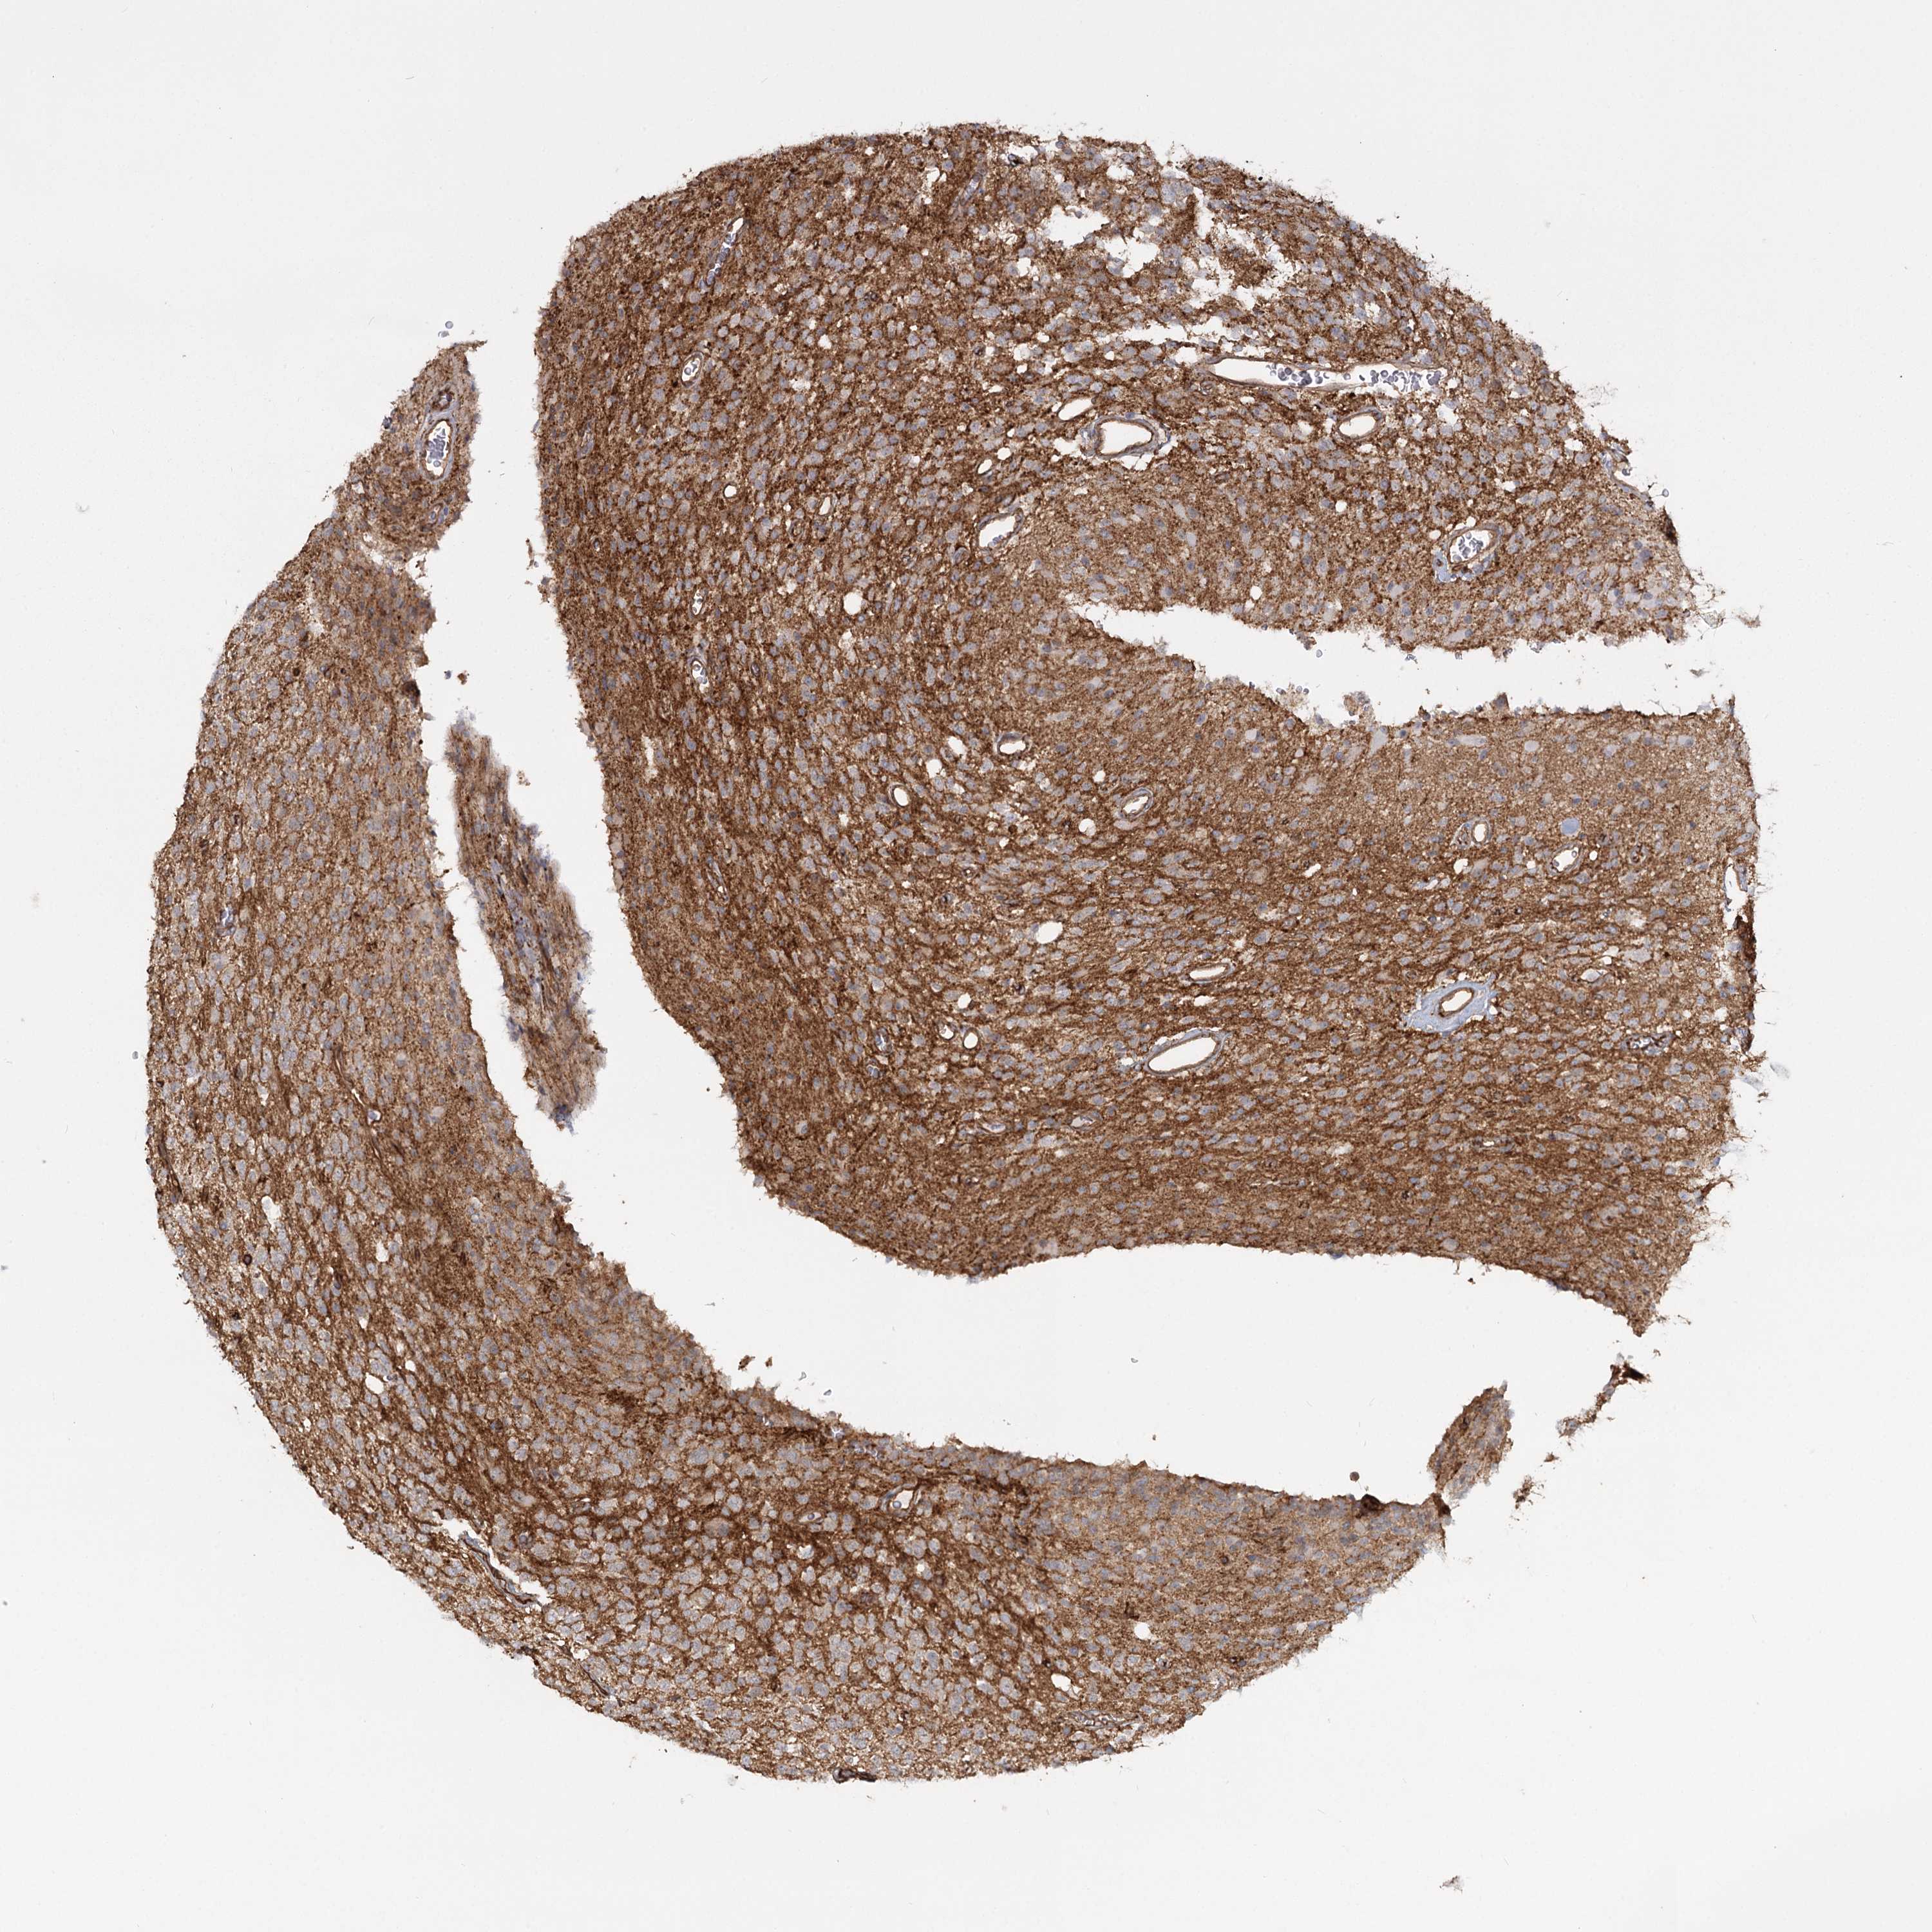

GLIOMA - Protein expressioni

A mouse-over function shows sample information and annotation data. Click on an image to view it in a full screen mode. Samples can be filtered based on level of antibody staining by selecting one or several of the following categories: high, medium, low and not detected. The assay and annotation is described here.

Note that samples used for immunohistochemistry by the Human Protein Atlas do not correspond to samples in the TCGA dataset.

Antibody stainingi

Antibody staining in the annotated cell types in the current human tissue is reported as not detected, low, medium, or high, based on conventional immunohistochemistry profiling in selected tissues. This score is based on the combination of the staining intensity and fraction of stained cells.

Each image is clickable and will lead to virtual microscopy that enables deeper exploration of all samples and also displays staining intensity scores, fraction scores and subcellular localization as well as patient and tissue information for each sample.

Antibody HPA036194

Staining

High

Medium

Low

Not detected

Intensity

Strong

Moderate

Weak

Negative

Quantity

>75%

75%-25%

<25%

None

Location

Nuclear

Cytoplasmic/membranous

Cytoplasmic/membranous,nuclear

Glioma, malignant, Low grade

Glioma, malignant, High grade

Glioblastoma, NOS